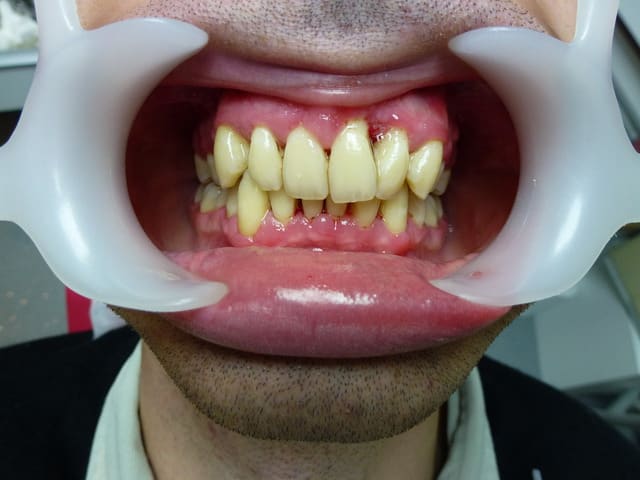

24 ans , propre sur lui, timide, très timide...

J'espère qu'il sera souriant sur sa photo de fin de traitement.

edit : septembre, octobre, novembre ouf!

je motive pour de l'odf...